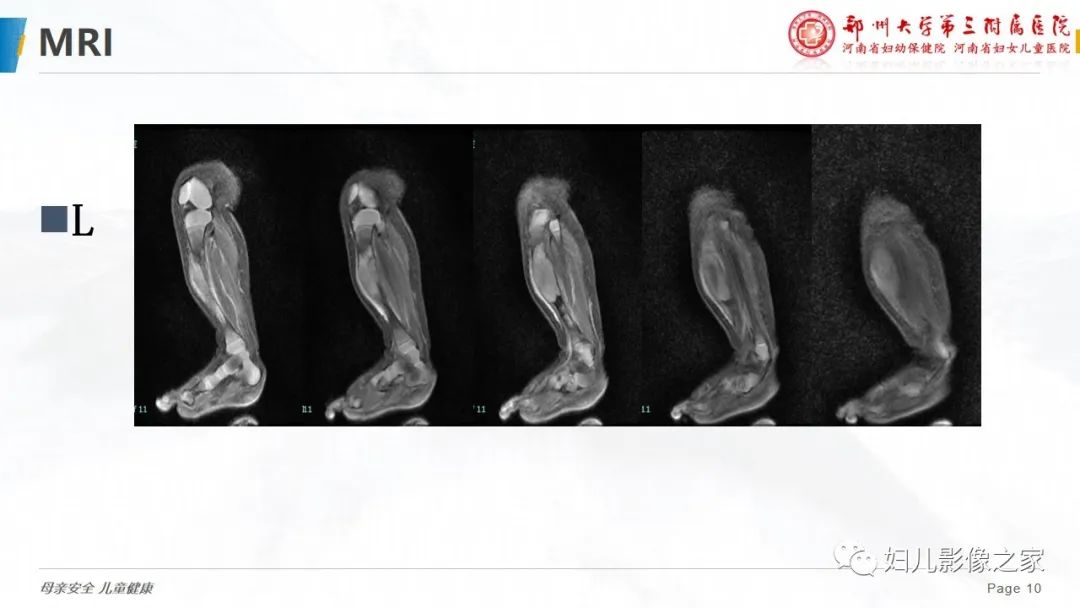

【PPT】骨纤维结构不良-10